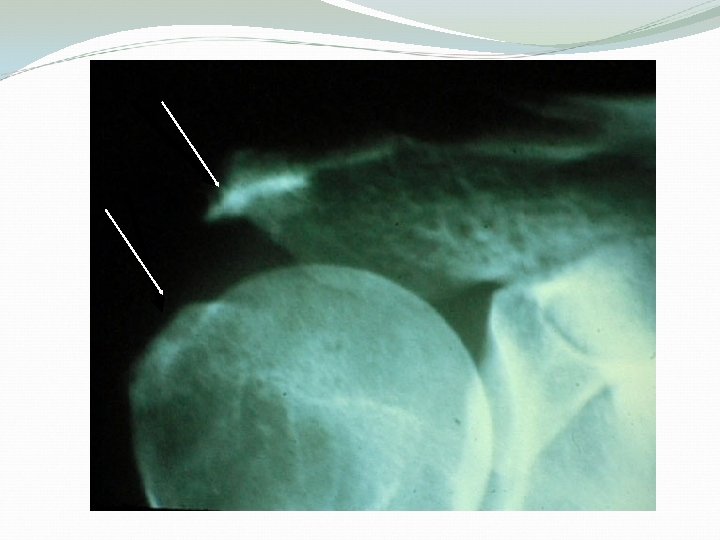

Radiological findings Plain X-rays: Acromial spurs AC joint osteophytes Subacromial sclerosis Greater tuberosity cyst MRI: To confirm the diagnosis and rule out rotator cuff tear